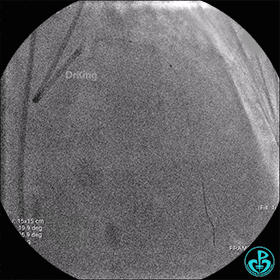

最后造影结果显示前降支3级血流,支架膨胀尚可。